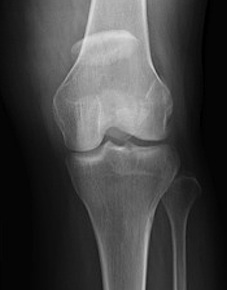

Non operative

Indications

Vertical

- biomechanically stable

Undisplaced transverse fractures

- < 2mm

- extensor mechanism intact

- able to straight leg raise